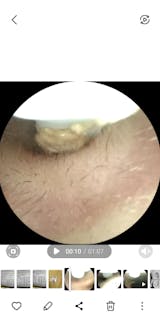

Ich habe eine starke Ohrenschmalzproduktion und es entstehen regelmäßig Propfen, die in der Vergangenheit regelmäßig vom Ohrenarzt entfernt werden mussten.

Mit diesel Gerät kann ich selbst in regelmäßigen Abständen das Ohr vom gröbsten Ohrenschmalz befreien. Mit diesem Gerät tut es überhaupt nicht weh, die Aufnahmen der Kamera sind sehr gut. Mit etwas Geduld, Übung und Vorsicht kann man das Ohr wirklich sehr gut reinigen, ohne es zu verletzen. Ich kann das Produkt ohne Vorbehalte weiterempfehlen und würde es wieder kaufen.

Dache das meine Ohren eigentlich sauber wären, aber naja, was soll ich sagen 😂

Meine Ohren waren soooo verstopft, das hätte ich mir nie gedacht. Hab aber zum Glück alles rausbekommen, das Gefühl ist auch richtig angenehm gewesen, fast schon satisfying